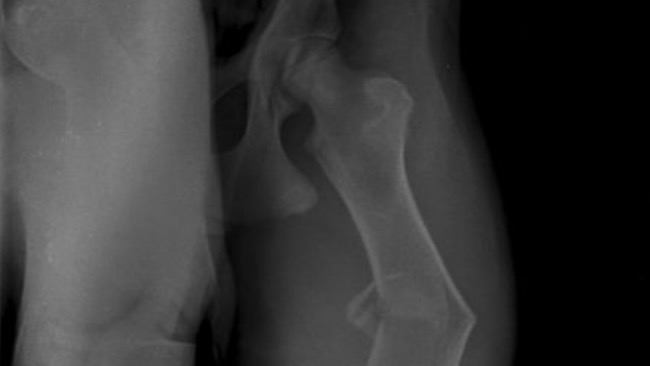

Lekarz zrobił zdjęcia i powiedział coś strasznego — że to złamanie z przemieszczeniem, i że to złamanie patologiczne, które wydarzyło się pod wpływem mojego własnego ciężaru.

To znaczy, że nie tylko trzeba naprawić moją nogę operacją…

ale też znaleźć powód, dlaczego to się stało.

Wczoraj leżałem cicho i słyszałem, jak Iwona rozmawia z panią doktor Marzeną. Mówiły o kolejnych badaniach, o szukaniu przyczyny, o tym, żeby taka sytuacja nigdy więcej się nie powtórzyła. Nie pamiętam nazw tych badań — wiem tylko, że Iwona bardzo się martwiła.